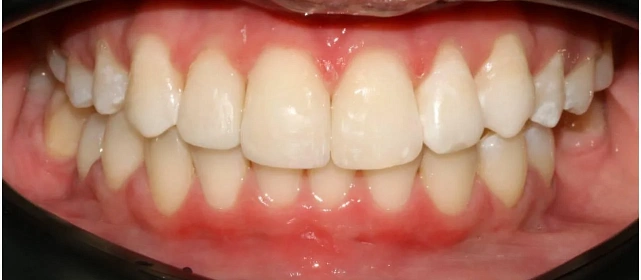

Проблема: В клинику обратилась пациентка — беспокоили неровные зубы и неправильное смыкание. Зубные ряды сходились некорректно, зубы стояли со смещением, что влияло и на внешний вид, и на распределение нагрузки при жевании.

Решение: Поставили элайнеры 3D Smile на обе челюсти. Лечение заняло 4 года и потребовало нескольких последовательных этапов коррекции. Капы менялись каждые 1–2 недели, на контрольных визитах отслеживали прогресс и выдавали новые наборы. Зубы встали в правильное положение, смыкание нормализовалось. Зафиксировали ретейнеры на обе челюсти, изготовили ретенционные капы. Пациентка прошла онлайн-консультацию с ортопедом для оценки дальнейших шагов.

Результат

Зубы выровнены, смыкание нормализовано. Установлены несъёмные ретейнеры на обе челюсти, изготовлены ретенционные капы. Пациентка предварительно проконсультирована ортопедом онлайн.